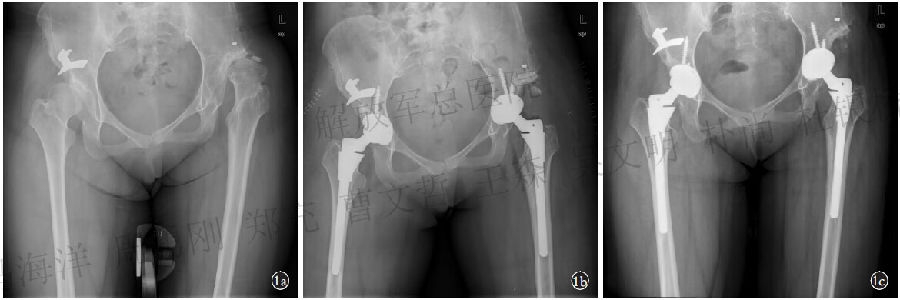

两组患者股骨假体均采用组配式S-ROM 假体。髋臼侧均采用生物固定臼杯辅助螺钉固定。56髋采用了Duraloc Option 杯,89髋使用Pinnacle 杯, 术中均采用直径为28 mm陶瓷头,其中87 髋采用SSTO,58 髋未采用SSTO。所有手术由我院同一名经验丰富的关节外科医生完成, 手术均采用后外侧入路。术中分离外旋肌群,打开关节囊,从股骨颈基底部切除股骨头。髂腰肌和部分臀大肌从股骨止点处松解,切除关节囊,暴露解剖臼。从偏向后下方骨量相对丰富的地方能够磨挫出43mm或44mm的臼从而置入44 mm Pinnacle杯或者46mm Duraloc Option杯,因而可以使用直径为28mm头的陶瓷对陶瓷界面。未采用SSTO复位:在股骨颈处行股骨近端截骨,截骨长度根据脱位高度术中决定。从股骨颈处逐渐向远端截, 直到股骨试模能够安全复位。所有Crowe Ⅳ型DDH股骨股骨近端截骨后尝试复位仍然困难时行SSTO(图1)。

图1 患者,女,28 岁,双髋关节发育不良继发骨性关节炎。左侧Crowe Ⅳ型,右侧加金属盖后转为Crowe Ⅲ型

1a.术前X 线片 1b.双髋置换术后X线片 1c.术后21个月复查X线片示髋关节功能良好,假体位置良好